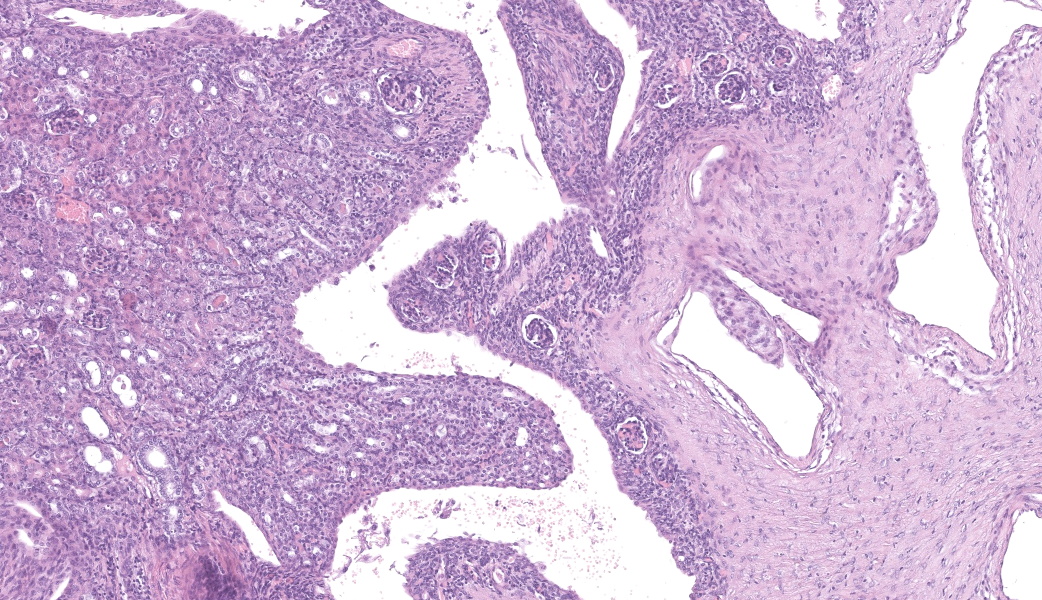

Left kidney: The left kidney is composed of multiple, largely dilated cavities that divide the kidney into numerous islands of parenchyma. These cavities are lined by 2–4 layers of cuboidal to highly columnar, eosinophilic epithelial cells with no mitotic activity (collecting ducts). Few sloughed epithelial cells and erythrocytes are present in the lumen of these ducts. The parenchyma contains islands of immature glomeruli with peripheral nuclei, poorly developed capillaries, and thickened Bowman’s capsule (vimentin positive). Primitive tubules are lined by large basophilic cuboidal epithelial cells with minimal or absent lumina. Other areas within the parenchyma consist of mature tubules and glomeruli with some tubules showing mild dilation and intraluminal protein casts. Collecting duct-like structures are multifocally surrounded by loosely arranged mesenchymal tissue (primitive mesenchyme). The interstitium is multifocally expanded by fibrous connective tissue and some areas are infiltrated by low to intermediate numbers of lymphocytes, plasma cells, macrophages, and occasional neutrophils. Some arteries are very prominent (large) with thickened media, and they appear tortuous. A medium sized artery is surrounded and infiltrated by inflammatory cells predominantely macrophages, neutrophils and occasionally multinucleated giant cells within adventitia, media and intima (transmural). Diffuse proliferation of fibroblasts and deposition of fibrin within the vessel wall is observed. Occasionally, the tunica intima is disrupted. Endothelial cell proliferation is evident with clustering of endothelial cells attempting to recanalize the affected lumina.

The large number of fetal glomeruli, presence of few primitive tubules, and occasional primitive mesenchyme, especially in a 5-week old mouse, certainly suggest a degree of renal dysplasia. Mouse kidneys should be completely developed within 4 days of birth (no later than 7 days).1,5 However, there was debate amongst conference attendees on whether this was a primary renal dysplasia or a secondary delay in maturation due to atrophy caused by congenital hydronephrosis/hydroureter. The fetal glomeruli were strikingly obvious in this case and are characterized by a reduction in the number of capillaries, the presence of podocyte nuclei that palisade around the periphery of a small glomerular tuft, decreased tuft segmentation, and a thick Bowman’s capsule. Immature glomeruli are, in a not-so-convoluted kidney, usually best seen in the subcapsular cortex.1,5 Glomeruli aside, however, while there were rare definitively primitive tubules, most participants thought that many of the tubules were atrophied in response to the severe hydronephrosis rather than truly dysplastic. This was further complicated by the complete lack of medullary distal convoluted tubules. Additionally, there were occasional glomeruli that were mature and the majority of the scant interstitium was relatively developed. As such, many conference participants preferred the term “asynchronous maturation” to describe the spectrum of development seen within the kidney.

The flocculent, cystic spaces made definitive interpretation of this case challenging. The lining of the cystic spaces resembled either persistent metanephric ducts (ducts in the outer medulla lined by pseudostratified, ciliated, columnar epithelium), transitional urothelium, and/or serosa. Metanephric ducts in the medulla potentially represented persistent, incompletely differentiated ureteric bud branches that did not differentiate into normal collecting tubes as they are supposed to, further suggesting a congenital etiology in this condition.5,10 The presence of serosa-lined spaces implies that some cysts had collapsed in on themselves during processing. Everyone unanimously agreed, however, that this was not polycystic kidney disease.

Differentiating between cystic renal dysplasia and polycystic kidney disease can be challenging, but there are some key differences to be aware of. Cystic renal dysplasia (CRD) is the most common pediatric renal disease in humans (and is also more common in most animals). It typically has larger cysts that are variably sized and lined by flat-cuboidal epithelium. CRD usually results from urinary tract obstruction and is often unilateral. It occurs sporadically and does not have a defined inheritance pattern like PKD. The characteristic findings for renal dysplasia will be present (fetal glomeruli, primitive tubules, primitive loose mesenchyme, +/- cartilaginous metaplasia, +/- mesenchymal collarettes), and there may or may not be vascular changes.4,10